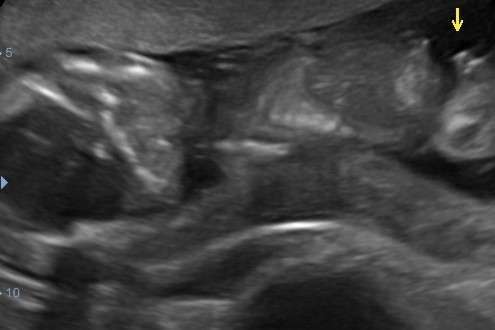

Had hem al geplaatst maar kan hem nergens terug vinden ❤️of 💙 echo is van gisteren met 16+6

Net de 13 weken echo gehad op 13 + 1. We zijn ontzettend benieuwd of iemand al kan zien wat het geslacht is/wordt! ☺️

Ik heb ook nog deze foto. Is dit een nub of niet? 😅

@nubster Net 13 weken echo gehad, wat denk jij? 🥰

Hier denk ik 💙 had je eerder een andere foto geplaatst?